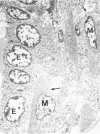

Myoepithelial cell tumors of the mammary gland have been observed in several mammalian species and are composed of a single cell type (myoepithelium) or, more often, present as a biphasic process including neoplastic ductal epithelial cells. In dogs, these are common tumors, but in humans they are rare neoplasms of the breast, and little is yet known of their pathogenesis, particularly with respect to myoepithelial origin. The present report describes bicellular mammary gland tumors arising from the duct epithelium that were induced in (C57BL/6NCr X DBA/2NCr)F1 (B6D2F1) mice by four weekly oral applications of 1 mg 7,12-dimethylbenz[a]anthracene (DMBA) starting at 8 weeks of age. Mammary tumors developed 7 to 8 months later in 14 of 57 mice, and most showed great morphologic resemblance to human adenomyoepitheliomas and myoepithelial carcinomas. Ultrastructurally, the induced tumors were composed of cuboidal epithelium with a microvillous border originating from the lining duct epithelium and plump oval or highly elongated cells that were identified as myoepithelial in origin. These spindle cells contained abundant microfilaments in parallel orientation, some with focal densities and intermediate filaments that frequently formed loose bundles or compact tonofibrils. The myoepithelial cells possessed well-developed desmosomes and plasma membrane caveolae and were regularly bordered by single or reduplicated basement membranes. By immunohistochemistry, strong immunoreactivity was observed for actin in the myoepithelial tumor component only, whereas cytokeratin was variably present in both duct epithelium and myoepithelium. Neoplastic myoepithelial cells stained purple with phosphotungstic acid hematoxylin (PTAH) and brilliant red with Masson's trichrome. It is suggested that DMBA-induced mouse mammary gland adenomyoepitheliomas and myoepithelial carcinomas may serve as very useful animal models to study myoepithelial tumorigenesis.